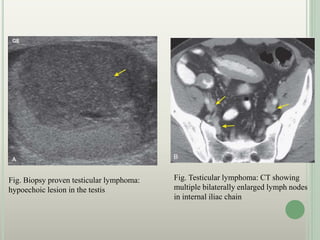

Fig. Biopsy proven testicular lymphoma:

hypoechoic lesion in the testis

Fig. Testicular lymphoma: CT showing

multiple bilaterally enlarged lymph nodes

in internal iliac chain